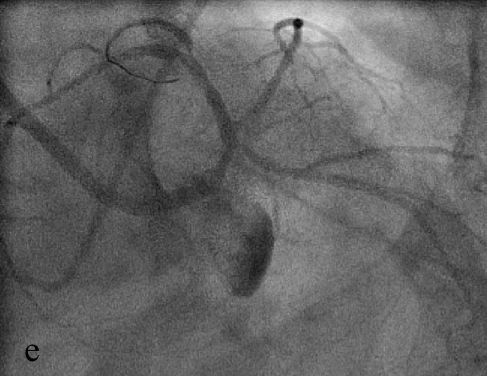

В связи с наличием выраженного стеноза устья ОВ (е) выполнена предилатация по методике «целующихся» баллонов (ж), после чего в ствол ЛКА с переходом на проксимальный сегмент ПМЖВ был имплантирован стент Cypher (з).